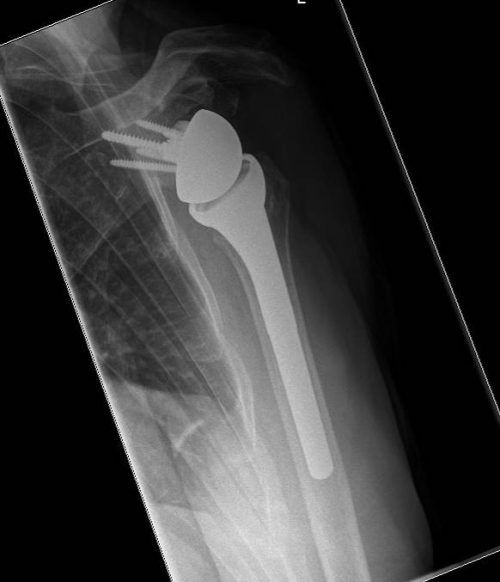

Gelenkersatz: Nicht jede Operation läuft nach Plan

München – Im Vergleich zu vielen anderen Eingriffen ist die Erfolgsquote beim Gelenkersatz eindrucksvoll: Weit über 80 Prozent der Patienten sind mit ihrer Endoprothese zufrieden. So nennt man die Ersatzteile aus Metall, Kunststoff und/oder Keramik, die dauerhaft im Körper verbleib